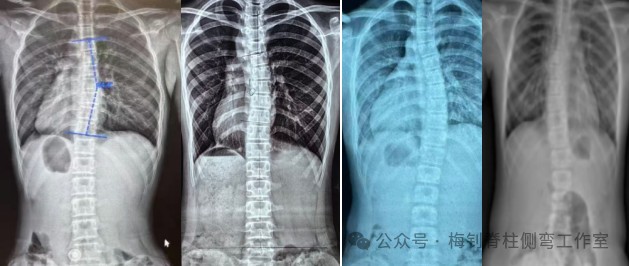

梅钊老师为大家讲解矫形器的原理、设计方法,以及穿戴过程中遇到的问题及解决办法。

课程中,梅钊老师对于平时经常遇到的问题做详细的讲解,如:设计矫形器时是否可以量化指标,如何处理三个平面的关系,矢状面生理曲度如何处理,如何平衡力线和角度等。大家踊跃提问,梅钊老师答疑解惑,学员们纷纷表示,听了梅老师的讲解后,豁然开朗,对于今后矫形器的设计有非常大的帮助。